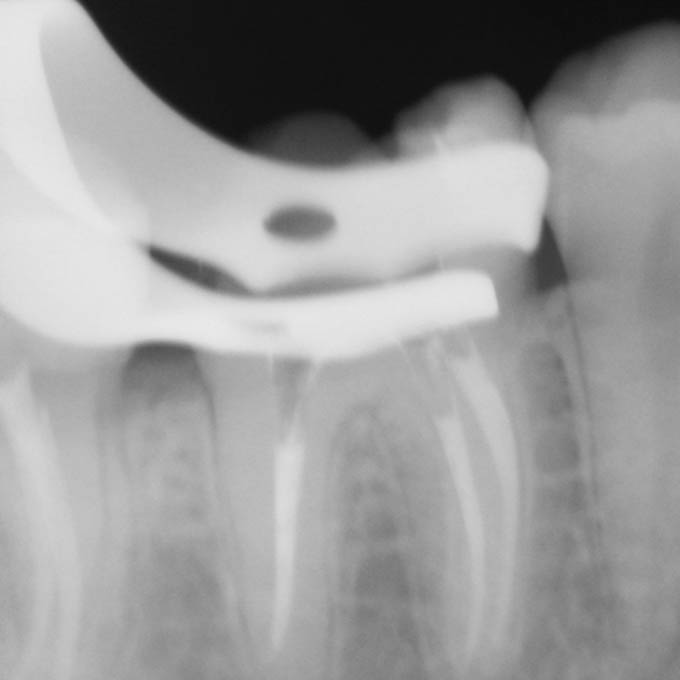

Зуб может иметь от 1 до 4 корневых каналов, а в редких случаях даже больше. Их диаметр зачастую не превышает 1 мм, поэтому увидеть какую-либо патологию и обеспечить ее эффективное устранение невооруженным глазом крайне сложно. Кроме этого, часто корневые каналы могут быть изогнутым, неровным, иметь ответвления, что еще больше усложняет задачу стоматолога. Микроскоп позволяет полностью решить эти проблемы.

С помощью микроскопа терапевт-эндодонтист лечит каналы зуба (перелечивает если каналы были ранее запломбированы) - удаляет инфекцию из корня, дезинфицирует, пломбирует специализированным антисептическим герметиком. При отсутствии инфекции в каналах киста на верхушке корня постепенно уменьшается в размерах и полностью исчезает.

Результат работы врача-эндодонтиста во многом зависит от того, каким образом будет восстановлена коронка зуба. Очень важно после лечения корневых каналов избежать повторного инфицирования каналов из полости рта. В зависимости от степени разрушения, зуб следует восстановить с помощью цельнокерамической вкладки или безметалловой коронки. Только в этом случае мы можем быть уверены, что зуб закрыт герметично и можем дать гарантию на лечение кисты.

Дентальный микроскоп — исключает риски ошибок

30-ти кратное оптическое увеличение в разы повышает точность диагностики и качество лечения корневых каналов.

Становится возможным определение скрытых каналов и ответвлений, трещин и перфораций корня.

Удаление только инфицированных тканей без повреждения здоровых.

3D пломбирование каналов — максимально герметичное лечение

Данный способ лечения каналов позволяет провести качественное равномерное трехмерное пломбирование даже сложных извилистых корневых каналов и микро-ответвлений горячей гуттаперчей без образования пустот.